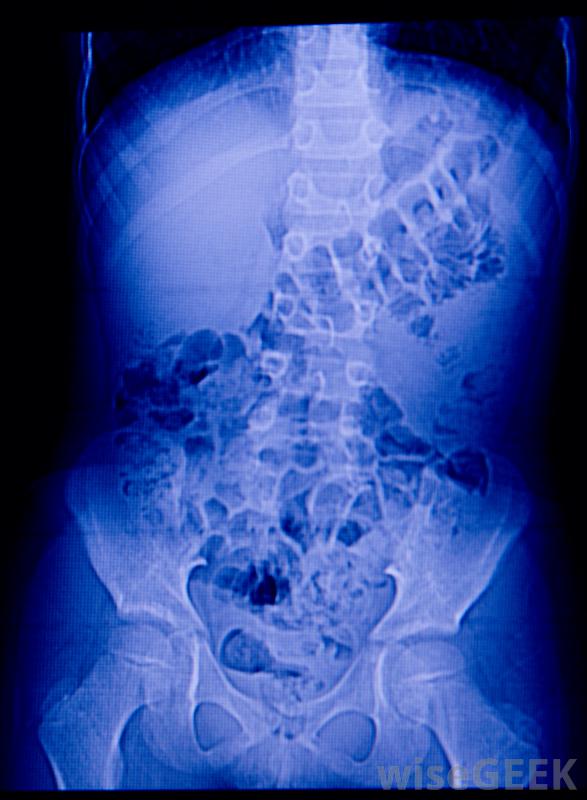

X光可以帮助检查肾脏感染引起的组织损伤一个人可以通过多种途径感染尿道。不良的卫生习惯会导致粪便细菌进入尿道,尤其是女性。性传播疾病、未消毒的妇科工具、生殖器急性损伤,自身免疫性疾病也会导致尿道和肾脏感染。很少情况下,肾结石或其他尿路阻塞会刺激肾脏内壁,增加细菌感染的风险

尿检通常用于帮助诊断肾脏感染初级保健医生通常可以通过评估患者的症状和收集血液和尿液样本进行实验室分析来诊断肾脏感染。如果医生不确定根本原因,他或她可能会将病人转介给肾脏科医生作进一步的诊断测试。专科医生可以检视化验结果,以识别特定的细菌,并进行x光检查,以检查组织损伤。在作出诊断后,医生可以决定最佳的治疗方案